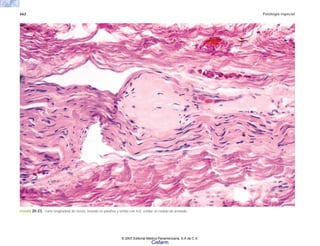

FIGURA 2-5. Histología de la piel en la esclerodermia, con abundante colágena por debajo del nivel de

las glándulas sudoríparas.